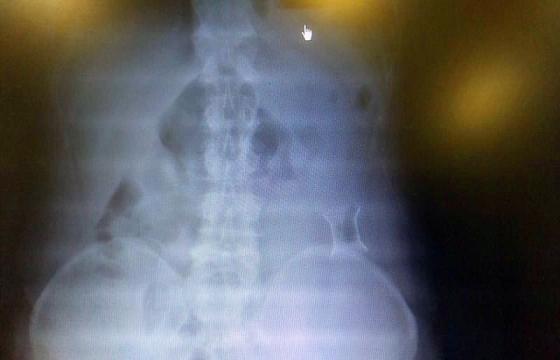

受試患者在結(jié)腸端端吻合術(shù)中,使用我司新研制產(chǎn)品達(dá)到了理想的預(yù)期效果。患者術(shù)后7天、14天X光片顯影,可降解腸道支架均能按研制設(shè)計(jì)的預(yù)期時(shí)間節(jié)點(diǎn)保持應(yīng)有強(qiáng)度,術(shù)后21天X光片顯示可降解腸道支架已完全破碎,并排出體外。在整個(gè)試驗(yàn)過程中,病患無任何不良反映,耐受良好。